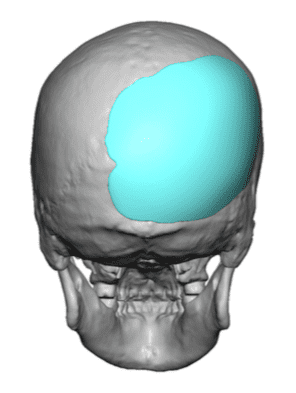

Patient 11

Desire to build out the back of his head which had bothered him his whole life.

Two-stage skull augmentation of the back of the head using a custom skull implant as the second stage. (first stage scalp expansion)